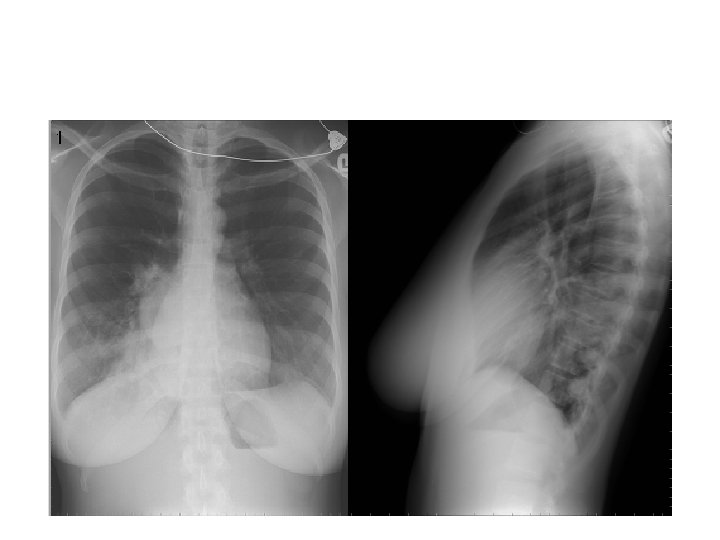

Final Diagnosis Intralobar Pulmonary Sequestration

History of recurrent pneumonia

Surgical Report • Intralobar Pulmonary Sequestration, treated with right lower lobectomy • Two major arteries from the thoracic aorta • Large vein draining sequestered lobe

Intralobar Pulmonary Sequestration (ILS) Characteristics • More common type • May present at any age • Generally as recurrent infection • No sexual predominance • Almost exclusively affects lower lobe • Arterial supply: descending aorta • Venous drainage: pulmonary veins